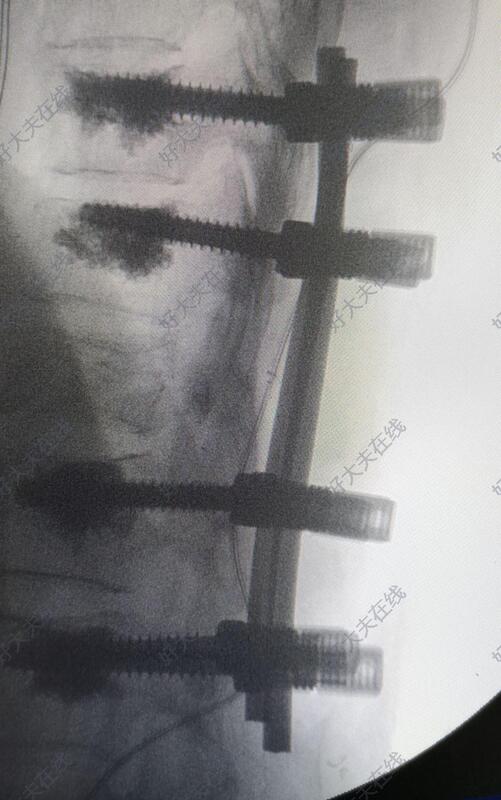

术中于胸10,胸11,腰1,腰2椎体置入骨水泥椎弓根螺钉。透视见骨折复位后,于胸12双侧椎弓根对胸12椎体植骨。